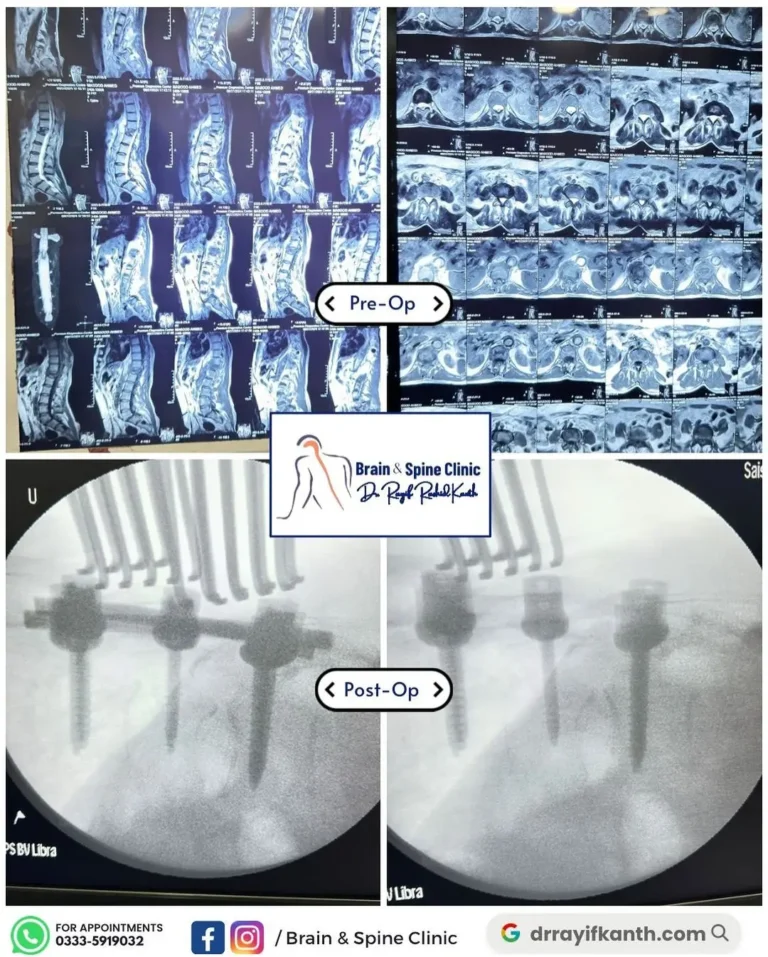

Recent Cases

Our Successful Surgery Cases